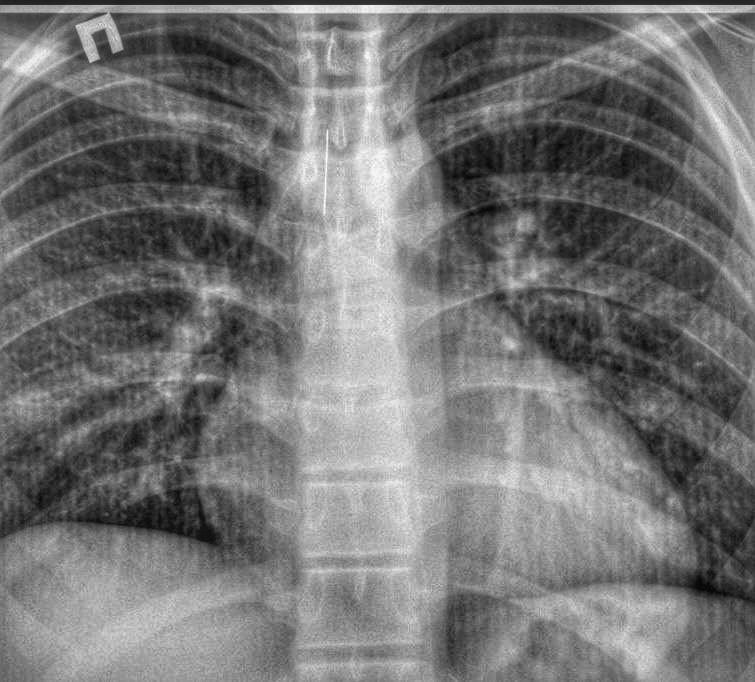

Клінічний випадок трапився 2 лютого. Підліток був доставлений до приймального відділення міської лікарні з одного з селищ району зі стороннім тілом в трахеї.

Завдяки високій кваліфікації чергового хірурга та анестезіологічної бригади, ендоскопічним методом було видалено стороннє тіло - голка довжиною 4 см.

Підлітку під наркозом провели бронхоскопію та дістали шпильку, яка гострим кінцем встромилася у слизову та нікуди не рухалася.

Гострий предмет міг викликати перфорацію - пробити легені або через стінку бронха потрапити і в серце. Наслідки могли бути трагічними.